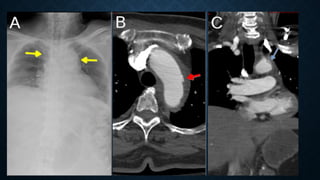

TRACHEAL INJURY IN A 32-YEAR-OLD MAN AFTER A THORACIC GUNSHOT WOUND. (A) AP RADIOGRAPH

SHOWS ENTRY AND EXIT SITES. THE AP BULLET TRAJECTORY WOULD BE EXPECTED TO INVOLVE MIDLINE

STRUCTURES SUCH AS THE TRACHEA. PARAMEDIASTINAL HAZINESS IS DEPICTED, REFLECTING PULMONARY

CONTUSIONS. (B) AXIAL CONTRAST-ENHANCED CHEST CT IMAGE SHOWS EXTENSIVE DIFFUSE

PNEUMOMEDIASTINUM. NOTE THE SMALL ANTERIOR TRACHEAL WALL DEFECT. TRACHEAL INJURY FROM A

PENETRATING WOUND WOULD LIKELY BE ASSOCIATED WITH INJURY TO OTHER ADJACENT MEDIASTINAL

STRUCTURES AS WELL. (C) PARASAGITTAL CONTRAST-ENHANCED REFORMATTED CT IMAGE SHOWS

EXTENSIVE ANTERIOR AND POSTERIOR PNEUMOMEDIASTINUM FROM THE VISUALIZED NECK TO THE ROOT

PULMONARY CONTUSION AND